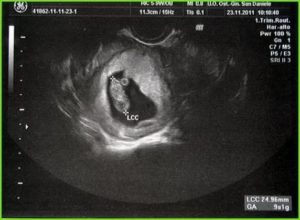

Отмечается увеличение желточного мешка, который находится в маточной полости. Он выглядит как колечко с диаметром 4 мм., на нем располагается зародыш.

Желточный мешочек выполняет функции питания, дыхания и кроветворения будущего малыша.

Для определения размеров эмбриона до двадцатой недели пользуются копчико-теменным размером (КТР), на поздних сроках можно определить предполагаемый рост ребенка от теменной части головы до пяток.